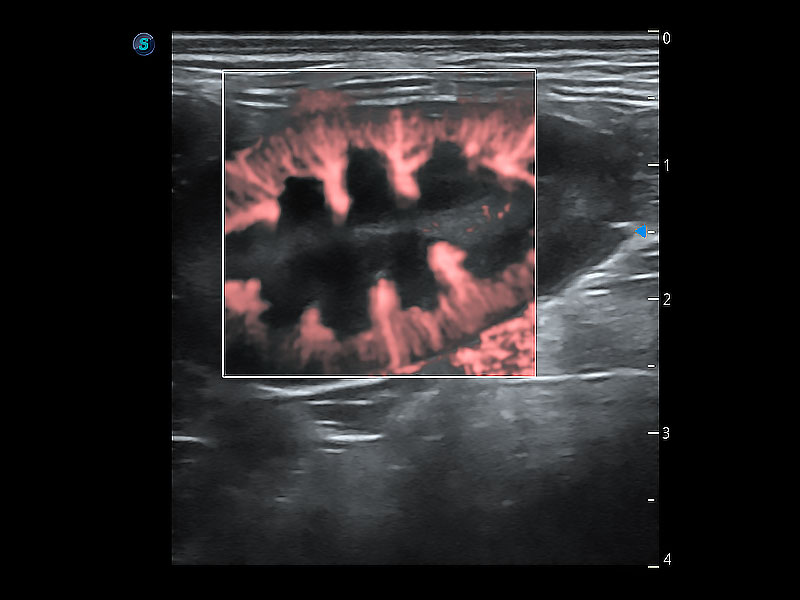

非线性融合造影成像充分利用谐波和基波信号,为难以观察的血流进行增强显像。可用于线阵、凸阵、微凸阵、相控阵探头。